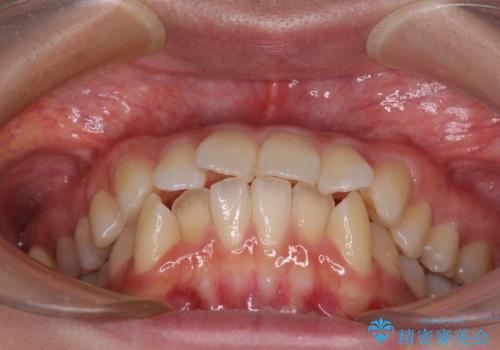

- 前歯のデコボコや口元の突出感、口の閉じにくさを気にして来院された患者様です。

上下左右第一小臼歯4本を抜歯し、ワイヤー装置にてデコボコを解消しながら口元を引っ込めるよう矯正治療を行うこととしました。